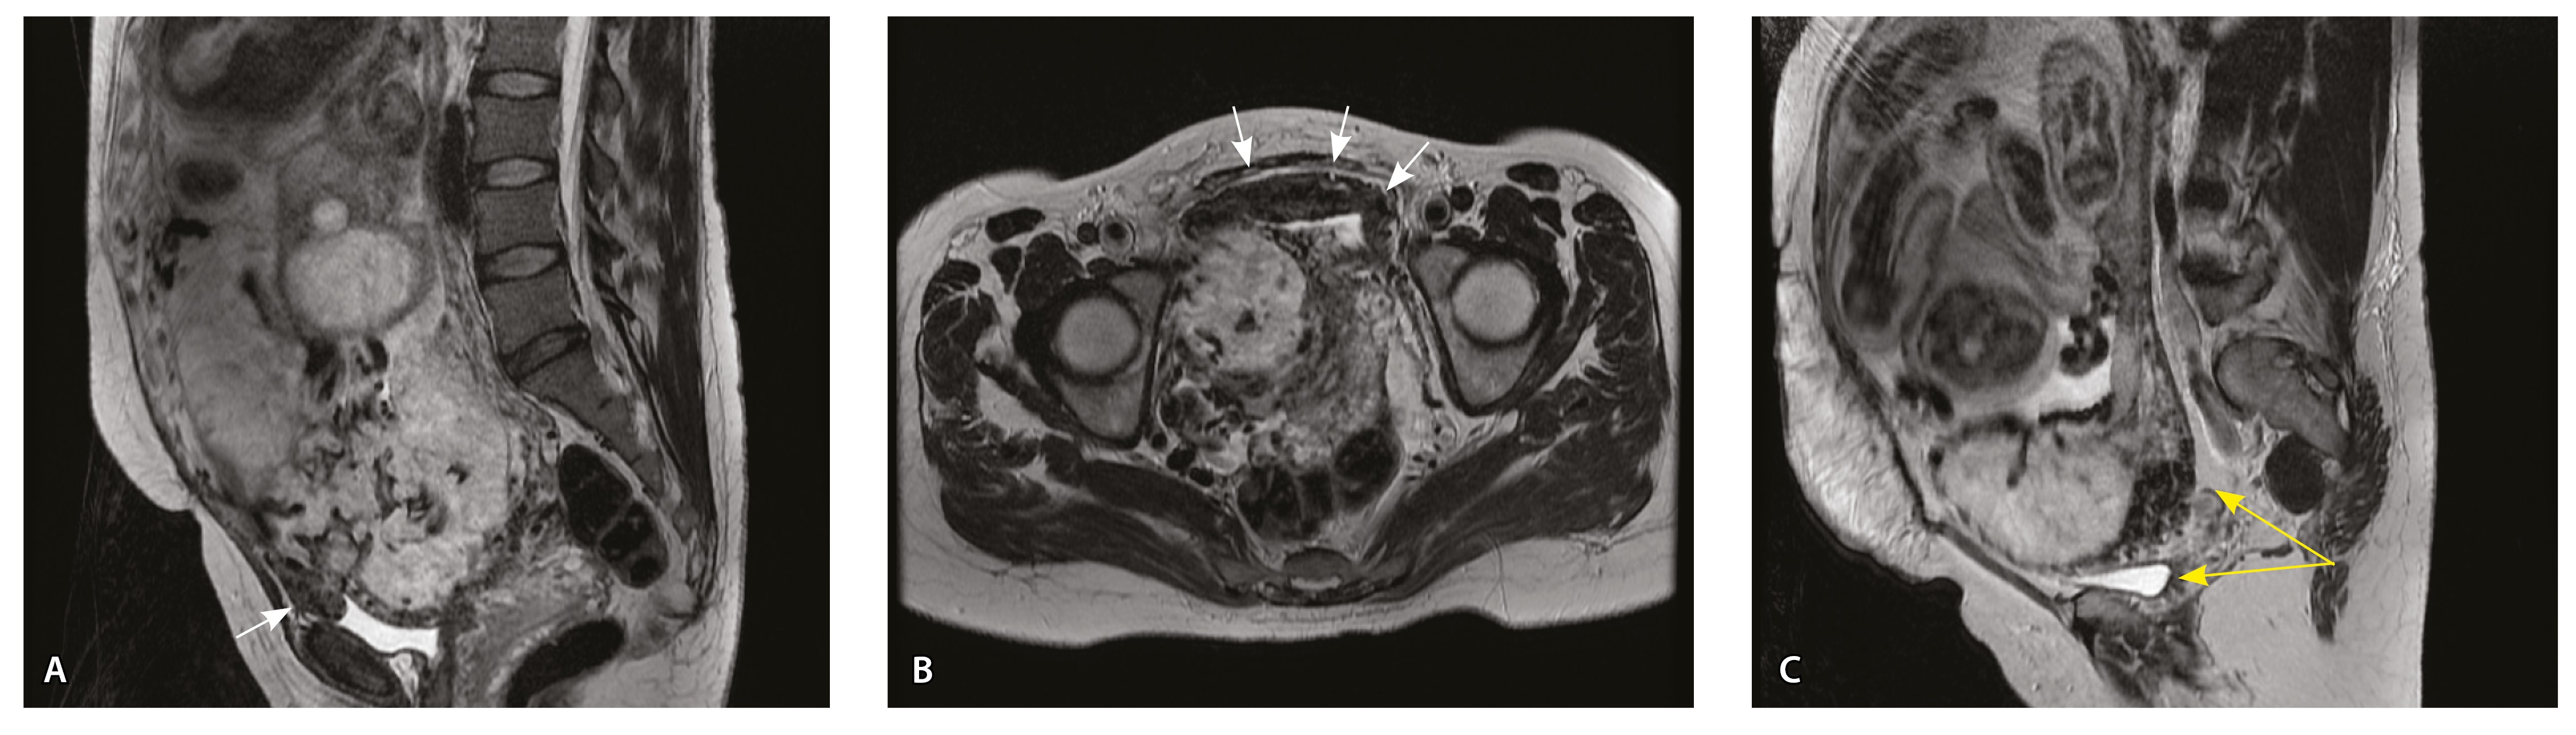

Сосуды 4-го типа. Наличие крупных извитых анастомозирующих сосудов, преимущественно по поверхности матки (в составе серозной оболочки матки) в сочетании с выраженным истончением нижнего сегмента матки (рис. 10).

Рис. 10. Беременность 33 недели, pl. percreta, PAS 3a по FIGO. На магнитно-резонансных томограммах в режиме Т2-взвешенного изображения в сагиттальной (A) и фронтальной (Б, В) плоскостях определяется внутриматочная гиперваскуляризация (желтые стрелки) и гиперваскуляризация в области выраженно истонченного нижнего маточного сегмента, с наличием многочисленных анастомозирующих сосудов по поверхности матки (белые стрелки); стенка матки в данной области представлена ретроплацентарными сосудами

Главным отличием крупных сосудов в составе серозной оболочки является то, что морфологически они находятся в пределах стенки матки. Об этом свидетельствует наличие в операционном материале тонкого поверхностного слоя мезотелия, отделяющего матку от брюшной полости (рис. 11). Его невозможно визуализировать методом МРТ из-за особенностей метода и толщины получаемых срезов.

Рис. 11. Сосуды 4-го типа при гиперваскуляризации стенки матки при патологической инвазии: А – крупный сосуд в составе серозной оболочки матки: справа видны единичные цитотрофобластические клетки (стрелки), не достигающие стенки артерии (иммуногистохимическое исследование, маркер цитокератин 8; × 50); Б – крупные сосуды в составе серозной оболочки: наличие внутреннего слоя эндотелиоцитов (иммуногистохимическое исследование, маркер СD34; × 50)

На микропрепаратах васкуляризация серозной оболочки представлена множеством крупных сосудов, идущих в разных направлениях и анастомозирующих друг с другом. Возможно, имеются артериовенозные соустья. На серийных срезах также видно, что в стенках артерий трудно различимы два слоя миоцитов (продольный и поперечный). Со стороны адвентиции они окружены толстым «футляром» из грубоволокнистой голубой ткани (при окраске по Маллори). Она проникает в стенку артерий, замещая мышечный слой (рис. 12).

Рис. 12. Истончение миометрия; в составе серозной оболочки видна крупная артерия, окруженная плотной соединительной тканью. А – cосуды в составе серозной оболочки (окраска по Маллори; × 200), не дифференцированная на мышечные оболочки стенка артерии, справа – вена, оба сосуда покрыты фиброзной оболочкой, внизу виден слой мезотелия в составе серозной оболочки; Б – серийный срез тех же сосудов при окраске на выявление эластических волокон, сосуд с соединительнотканной муфтой (окраска по Вейгерту; × 50): определяется полная дезорганизация эластичного материала в стенке; стрелкой указан мезотелий (аналог pl. increta, PAS 2 по FIGO)

Эластический каркас представлен сетью тонких волокон, без концентрации на внутреннюю и внешнюю мембраны. Однако маркер СD34 констатирует сохранение эндотелия, что свидетельствует о том, что по артериям циркулирует кровь, не сворачиваясь (рис. 13).

Рис. 13. Самые крупные сосуды в пределах серозной оболочки стенки матки: А, Б – серийные срезы артерии; × 50. При окраске по Маллори (А) видна тонкая полоска мезотелия (черная стрелка), слабо дифференцированная мышечная стенка артерии, вокруг нее – плотная коллагеновая оболочка (желтая стрелка), в просвете определяются тромботические массы. При окраске по Вейгерту (Б) наблюдается полная потеря внутренней и внешней эластических мембран

Анализ частоты встречаемости сосудов 4-го типа при различных степенях приращения плаценты (рис. 14) показал: при плотном прикреплении плаценты (gr 2) и поверхностном приращении (gr 3) сосуды данного типа не выявлены, при pl. increta (gr 4) частота встречаемости незначительная – 16,7%, а при глубокой инвазии плаценты (pl. percreta, gr 5) сосуды этого типа преобладают (р < 0,001, хи-квадрат Пирсона).

Сосуды 4-го типа встречались как при pl. increta (16,7%) (PAS 2 по FIGO), так и при pl. percreta (100%) в пределах серозного слоя матки (PАS 3a по FIGO). Обнаружено наличие крупных извитых анастомозирующих сосудов, преимущественно по поверхности матки, в сочетании с выраженным истончением рубца от КС. Главное отличие сосудов этого типа – локализация в пределах серозного слоя матки, с наличием тонкого поверхностного слоя мезотелия на микропрепаратах по их поверхности. Этот феномен можно объяснить тем, что в случае прикрепления трофобласта и затем плаценты к рубцу от КС при прогрессировании беременности плацента оказывает паракринное влияние в том числе посредством факторов ангиогенеза, в результате чего нельзя исключить рост сосудов из бассейнов маточных артерий с целью обеспечения трофической функции матки и сохранения беременности. Указанный патогенетический механизм также подтверждают описанные в литературе случаи брюшинной беременности [17]. Кроме того, нельзя исключить, что локальная ишемия стенки матки в области врастания может способствовать увеличению ангиогенеза и васкулогенеза. При выполнении МРТ невозможно достоверно визуализировать серозный слой матки из-за его малой толщины, поэтому создается впечатление о локализации сосудов за пределами стенки матки. По данным патоморфологического исследования, для этого типа характерно наличие крупных сосудов, анастомозирующих друг с другом. В стенках артерий трудно различимы 2 слоя миоцитов, по наружной поверхности сосуды окружены толстым «футляром» из грубоволокнистой соединительной ткани, которая проникает в стенку артерий и замещает мышечный слой. Эластический каркас представлен сетью тонких волокон, без концентрации на внутреннюю и внешнюю мембраны. Генез возникновения таких сосудов до конца не изучен. В ряде исследований, посвященных беременности, расположенной в проекции рубца от КС, отмечается наличие артериовенозных соустий по типу мальформации в данной области даже на ранних сроках беременности, которые, возможно, продолжают функционировать и на более поздних сроках и становятся еще более полнокровными [18–20].